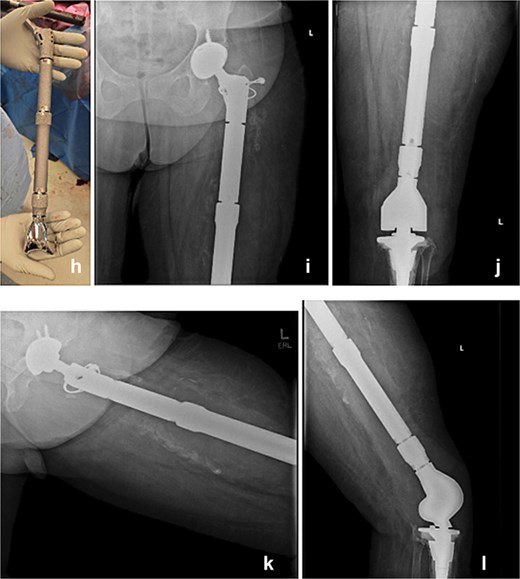

Seven days later, reimplantation was performed. A press-fit cup with a dual mobility liner was placed in the acetabulum to reduce dislocation risk. A modular TFR system was used: proximally, a femoral stem compatible with the dual mobility head; distally, a rotating-hinge knee mechanism attached to a tibial stem. Soft-tissue reconstruction was performed as feasible. The wound was closed over a drain and protected with a negative-pressure dressing. The patient remained non-weight-bearing with a knee immobilizer and continued intravenous cefazolin postoperatively for six weeks.

Postoperatively, early imaging confirmed appropriate implant alignment. Motor function was preserved, and the incision healed without complication. She began a structured rehabilitation program with gradual progression to protected ambulation using an orthotic knee brace. At follow-up, the patient demonstrated functional limb

use, no signs of recurrent infection, and a stable prosthesis without evidence of hardware failure (Fig. 3).

The modular TFR implant (h) is grossly visualized prior to implantation. Immediate postoperative anteroposterior (i and j) and lateral (k and l) radiograph following definitive reimplantation, showing the modular total femur replacement with a dual mobility acetabular component proximally and a rotating-hinge knee mechanism distally in appropriate alignment.